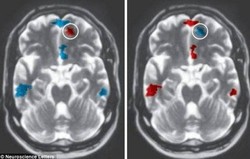

- 공룡, 왜 멸종했을까?

- © 브레이크뉴스공룡 멸종 이유가 여러 가지 제기된 가운데 미국에서 ‘소행성 충돌설’이 거론됐다. 공룡 멸종 이유를 두고 연구진들의 다양한 의견 ...